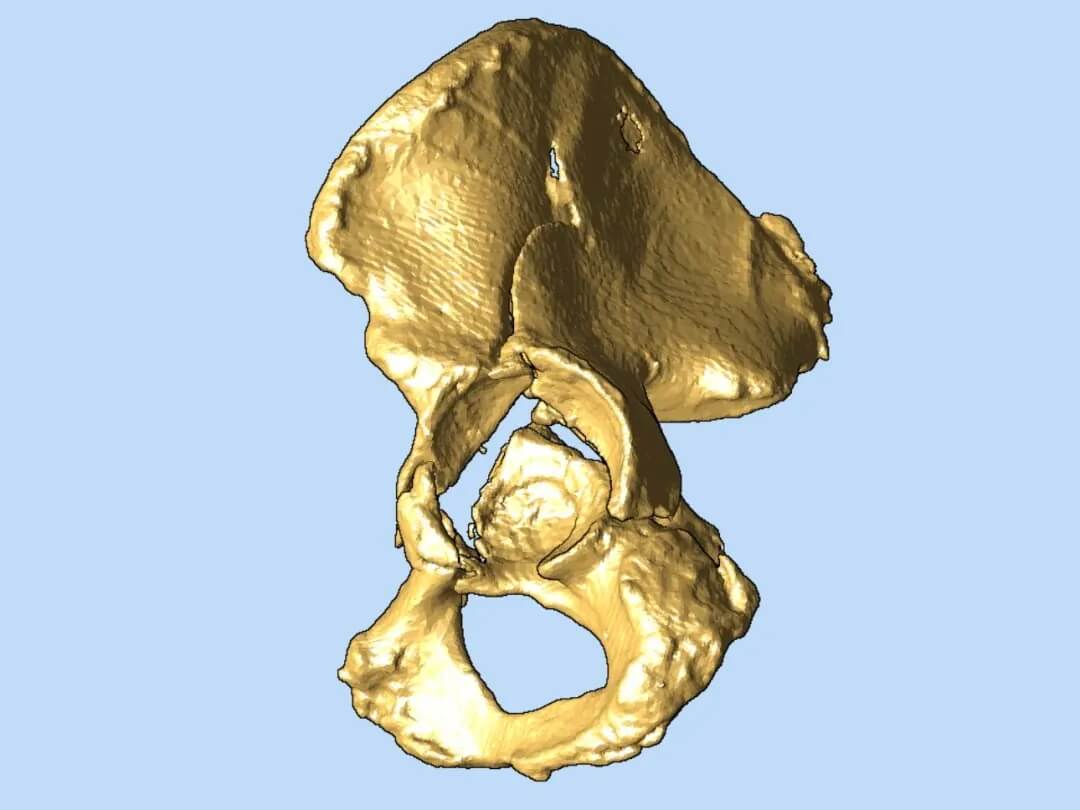

在腔靜脈濾器成功植入,患者安全度過(guò)血栓脫落風(fēng)險(xiǎn)的高危期后,羅軍團(tuán)隊(duì)將利用先進(jìn)的3D打印技術(shù),為患者量身定制骨盆骨折修復(fù)方案。基于患者CT數(shù)據(jù)打印出的1:1精準(zhǔn)骨盆模型,能讓醫(yī)生在術(shù)前清晰掌握粉碎骨塊的形態(tài)、位置,實(shí)現(xiàn)極致的手術(shù)可視化和方案?jìng)€(gè)性化,顯著提高手術(shù)精準(zhǔn)度、減少創(chuàng)傷、縮短手術(shù)時(shí)間,最終目的是促進(jìn)患者獲得最佳的功能恢復(fù)。